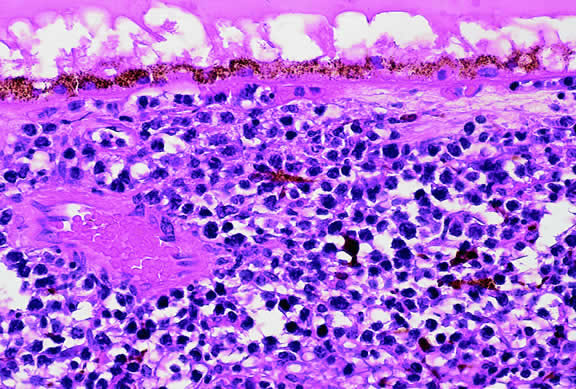

Histopathology

The cells comprising uveal melanoma constitute a biologic spectrum comprising bland spindle A melanoma cells at one end and wildly anaplastic epithelioid cells at the other. The term spindle cell is derived from the fusiform or spindled configuration of the cells' cytoplasmic outline. They are bipolar in shape, and many have long tapering processes that occasionally are highlighted when individual pigmented cells are seen in a largely amelanotic tumor. Spindle cells grow in a syncytial fashion forming interweaving fascicles of parallel oriented cells (Fig. 30). The cells can be pigmented or nonpigmented. Two types of spindle cells are recognized; spindle A and spindle B. These are distinguished by their nuclear characteristics. Spindle A nuclei are tapering ovals or cigar-shaped and have finely dispersed chromatin (Fig. 31). If a nucleolus is present, it usually is inconspicuous. Many spindle A cells have a longitudinally oriented chromatin stripe that actually is caused by a fold in the nuclear membrane. The nuclei of spindle B cells have distinct nucleoli and coarser chromatin and tend to be plumper and more oval in shape (Fig. 32).

Fig. 30. Amelanotic spindle cell melanoma. Tumor is composed of interweaving fascicles of spindle cells. Photomicrograph shows longitudinally and transversely sectioned fascicles. (Hematoxylin-eosin, × 100.)